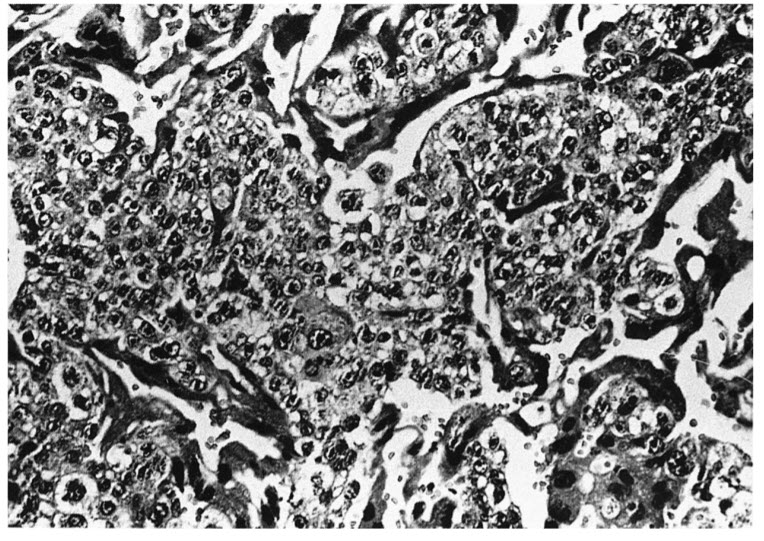

The figure is an example of choriocarcinoma, showing sheets of malignant trophoblasts. Malignant choriocarcinoma is a transformation of molar tissue or a de novo lesion arising from the placenta. There are significant degrees of cellular pleomorphism and anaplasia. Choriocarcinoma can be differentiated from invasive mole by the fact that the latter has chorionic villi and the former does not.